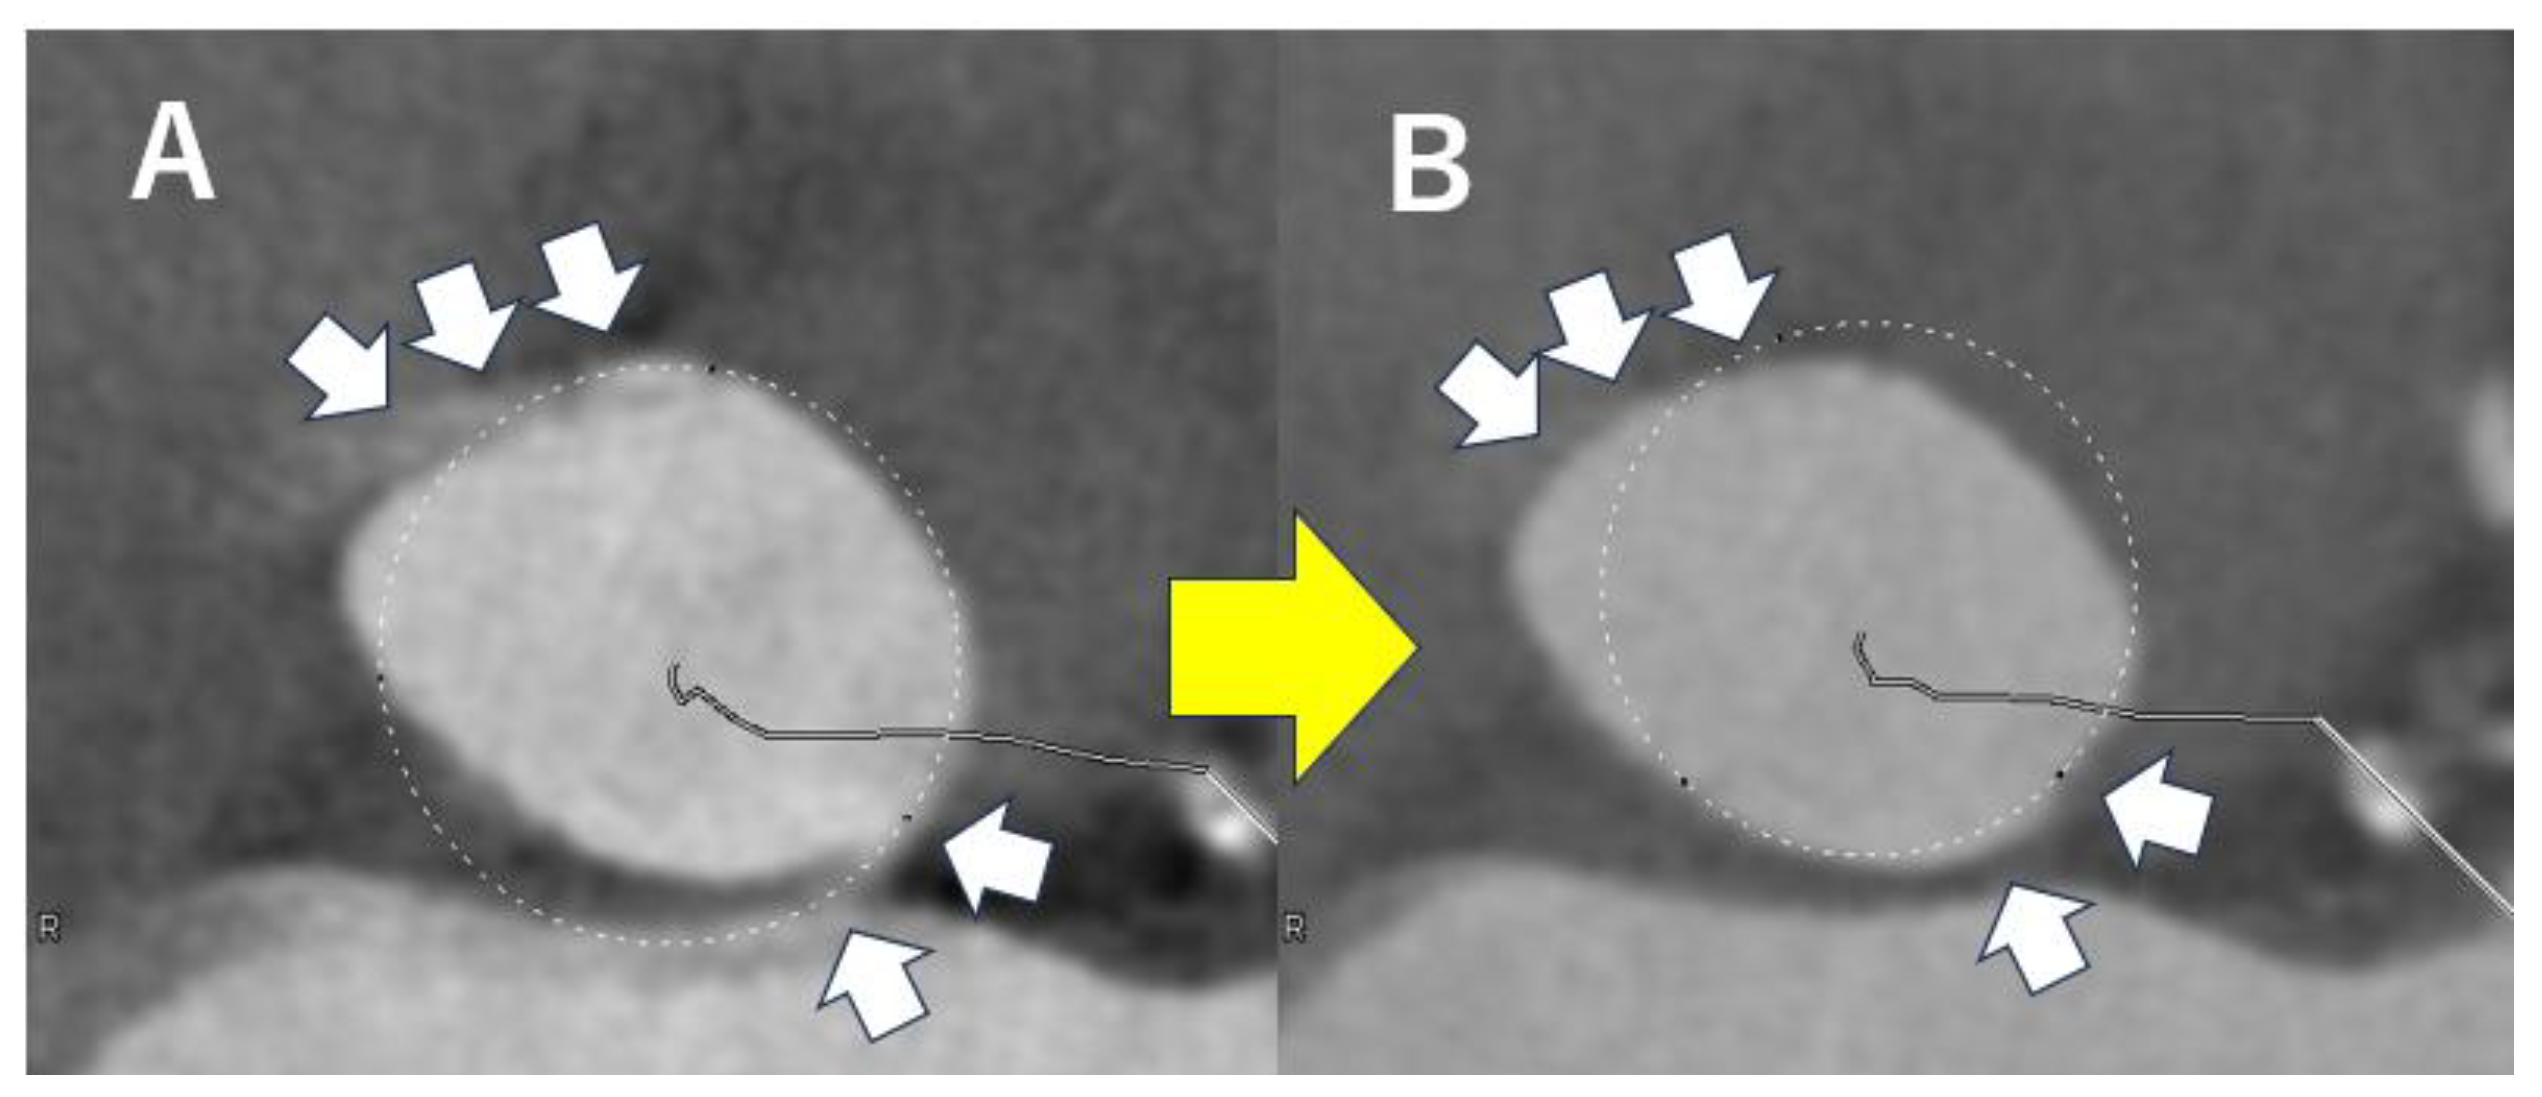

4.2. Analysis of Aortic Valve Complex on CT Before TAVI

4.3. Analysis of Catheter Access Route on CT Before TAVI

- Yucel-Finn, A.; Nicol, E.; Leipsic, J.A.; Weir-McCall, J.R. CT in planning transcatheter aortic valve implantation procedures and risk assessment. Clin. Radiol. 2021, 76, 73.e1–73.e19. [Google Scholar] [CrossRef]